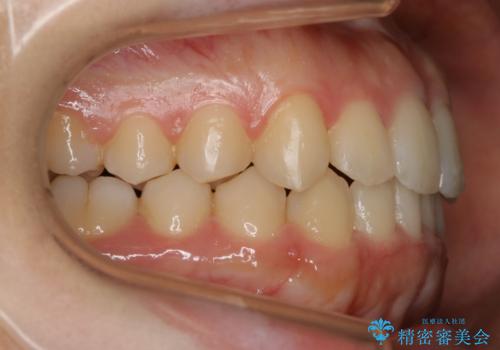

【非抜歯】すきっ歯と噛み合わせの治療

- 上の前歯のすきっ歯と下の前歯のガタつきを主訴にご来院されました。

噛み合わせの改善も同時に進めつつ、主訴の部分も効率的に治していくためマウスピース装置でゴムかけを行いながら治療を進めていきました。

正中離開(すきっ歯)

真ん中の歯が左右に開いてしまい隙間ができてしまう状態を「正中離開」といい、俗にすきっ歯と呼ばれています。

隙間を埋めていく方向に歯を移動させることで改善していくケースが多く、比較的治りやすい不正咬合のひとつとされています。

しかしながら、歯が捻じれていたり、噛み合う歯との位置関係によっては治療が難しくなる場合があります。